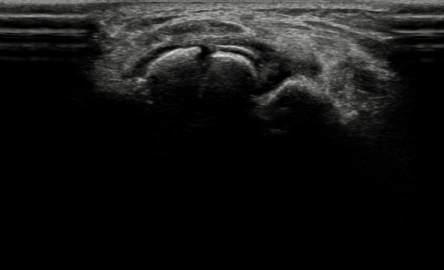

수술 전

2022.06.08